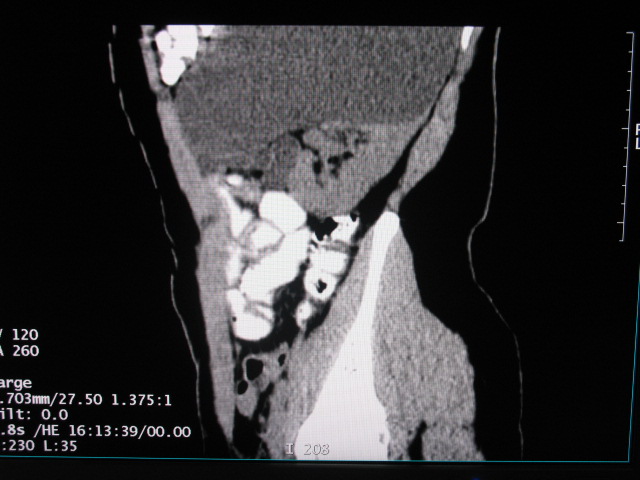

女,28岁,自觉腹部包块一年余

左侧为扩张的输尿管,一直延续到膀胱,那么它的上端应该是扩张的肾盂,但是在他的下方我们看到一个比较正常的肾,所以考虑左侧重复肾盂输尿管畸形。

考虑左侧双肾盂双输尿管畸形,其中一输尿管末端梗阻(不排除异位开口可能)并相应之肾盂及输尿管明显扩张积水。

考虑左侧双肾盂双输尿管畸形,其中一输尿管末端梗阻并输尿管肠管样扩张盂曲、肾盂囊状扩张积水。

支持;左侧双肾盂双输尿管畸形,其中一输尿管末端梗阻并输尿管肠管样扩张迂曲、肾盂囊状扩张积水。

考虑左侧双肾盂双输尿管畸形,其中一输尿管末端梗阻(不排除异位开口可能,不知病人有无不自觉溢尿,有可能开口于阴道或宫颈,也可下端为盲端)并相应之肾盂及输尿管明显扩张积水。

术后证实是左侧双肾盂双输尿管畸形,巨输尿管巨肾盂症